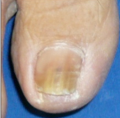

1.爪白癬

爪白癬の治療の第一選択は飲み薬です。塗り薬ではなかなか治りません。